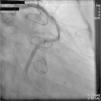

A 67-year-old woman with a history of coronary artery bypass grafting (CABG) six months previously underwent coronary angiography for stable class III angina. Extensive thrombus burden was visualized in the mid-distal segment of the saphenous vein graft (SVG) to the second obtuse marginal branch with decreased Thrombolysis In Myocardial Infarction (TIMI) 2 flow (Figures 1 and 2) and without evidence of obstructive atherosclerosis. The patient was placed on oral anticoagulation with rivaroxaban (Janssen Pharmaceuticals, Titusville, NJ, USA) 20 mg once daily. Follow-up catheterization after four weeks revealed angiographic resolution of the thrombus with significantly improved TIMI 3 flow (Figures 3 and 4).